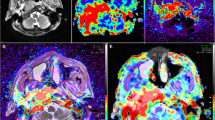

The 55 patients with NPC demonstrated greater tumor perfusion than that of surrounding tissues on the ASL pseudocolored maps (Figs. 3c and 4c). Pre-TBF was 146.70 ± 21.39 mL·100 g−1·min−1 and Post-TBF was 84.18 ± 11.56 mL·100 g−1·min−1, the paired sample t-test indicated significantly reduced tumor perfusion after treatment (p < 0.001; Fig. 3g and 4g). For the PR group, the Pre-TBF value was 158.46 ± 15.74 mL·100 g−1·min−1, Post-TBF value was 91.01 ± 12.42 mL·100 g−1·min−1, and ΔTBF was 66.81 ± 14.20 mL·100 g−1·min−1. For the SD group, the Pre-TBF value was 129.41 ± 17.94 mL·100 g−1·min−1, Post-TBF value was 79.22 ± 9.55 mL·100 g−1·min−1, and ΔTBF was 46.69 ± 18.63 mL·100 g−1·min−1, The independent sample t-test showed significant differences between the inter-group measurements. For the residual group, the Pre-TBF value was 129.34 ± 19.67 mL·100 g−1·min−1 and ΔTBF was 50.15 ± 20.24 mL·100 g−1·min−1; for the non-residual group, the Pre-TBF value was 154.47 ± 17.32 mL·100 g−1·min−1 and ΔTBF was 68.05 ± 14.62 mL·100 g−1·min−1. The independent sample t-test showed significant differences between the inter-group measurements. There were no differences in Post-TBF between the residual group and the non-residual group (Table 4, Fig. 5). Pre-TBF and ΔTBF showed significant positive correlations with the tumor atrophy rate; the correlation coefficients were 0.677 and 0.567, respectively (Fig. 6).

A male patient aged 57 years with stage III nasopharyngeal carcinoma (T3N2MO). Pathological examinations suggested non-keratinizing undifferentiated squamous cell carcinoma. Before treatment, T2-IDEAL and T1WI images revealed nasopharyngeal masses on the right around the right levator veli palatini, tensor veli palatini, and internal carotid artery (a and b); the ASL series integrated with BRAVO series revealed high mass perfusion (c) with a TBF value of 110.34 mL·100 g−1·min−1; the maximum primary tumor diameter measured on axial T1WI enhanced imaging was 37.84 mm (d). Re-examination after the prescribed dose reached 40 Gy suggested minor tumor shrinkage (e and f) and slightly high mass perfusion (g), with a TBF value of 100.32 mL·100 g−1·min−1; the maximum primary tumor diameter measured on axial T1WI enhanced imaging was 36.14 mm (h). Follow-up examination one month after chemoradiotherapy completion revealed a residual tumor (arrows in i)

A male patient aged 48 years with stage IVA nasopharyngeal carcinoma (T4N2MO). Pathological examinations suggested non-keratinizing undifferentiated squamous cell carcinoma. Before treatment, T2-IDEAL and T1WI images revealed nasopharyngeal masses on the right invading the sphenoid sinus (a and b); the ASL series integrated with BRAVO series revealed high mass perfusion (c) with a TBF value of 170.67 mL·100 g−1·min−1; the maximum primary tumor diameter measured on axial T1WI enhanced imaging was 45.92 mm (d). Re-examinations after the prescribed dose reached 40 Gy revealed notable tumor shrinkage (e and f) and reduced tumor perfusion (g) with a TBF value of 107.73 mL·100 g−1·min.−1; the maximum primary tumor diameter measured on axial T1WI enhanced imaging was 24.34 mm (h). Follow-up examination one month after chemoradiotherapy completion revealed no residual tumor (i)